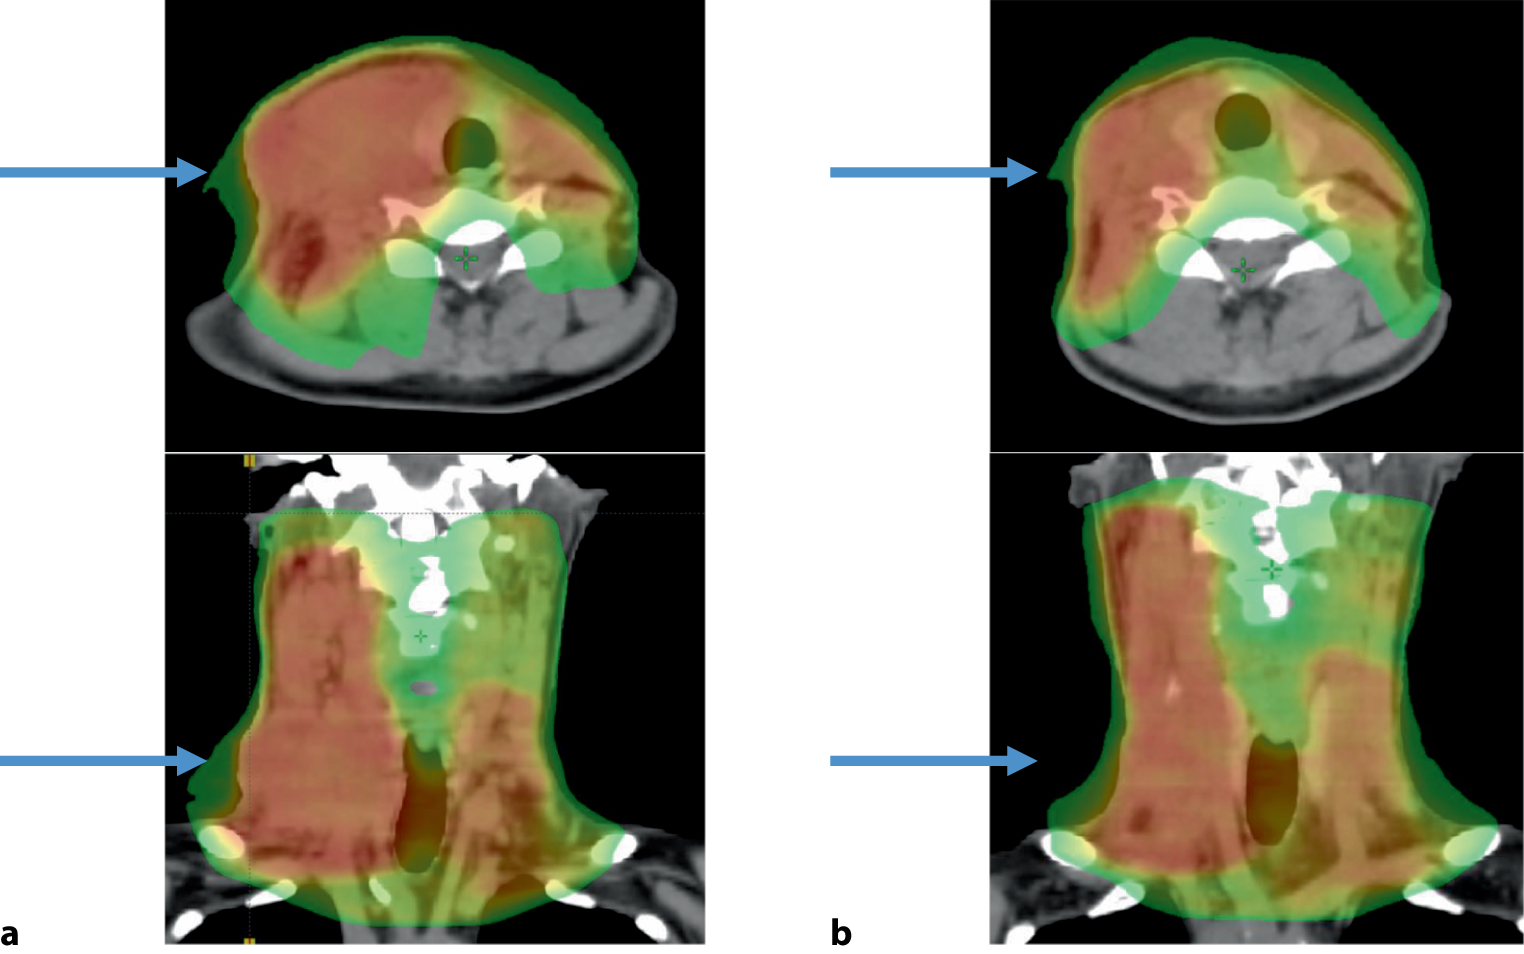

With technological improvements in RT delivery leading to better dose conformity, such as IMRT, volumetric arc radiotherapy (VMAT) and proton therapy, additional attention may be dedicated to reducing the overall RT dose to healthy tissue without compromising the tumour dose. A reduction in the dose to critical structures, e.g. the salivary glands, resulted in reduced long-term toxicity and improved quality of life [12]. Together with improved target definition using advanced imaging (magnetic resonance imaging [MRI], PET/CT), improved accuracy of radiation delivery using image-guided radiotherapy (IGRT) and even reacting to tumour volume changes during the treatment course through image-guided adaptive radiotherapy (IGART), the overall toxicity can be reduced without treatment de-intensification to the tumour site ([13], Figs. 2 and 3).

Fig. 3

Anatomic changes during a course of radiotherapy (a treatment start, b after 44 Gy) impacting the dose distribution

Bild vergrößern

Radiotherapy should use modern techniques, for example IMRT, VMAT, image guidance and online treatment adaptation, aiming to reduce side effects without compromising the oncologic outcome (Fig. 3).